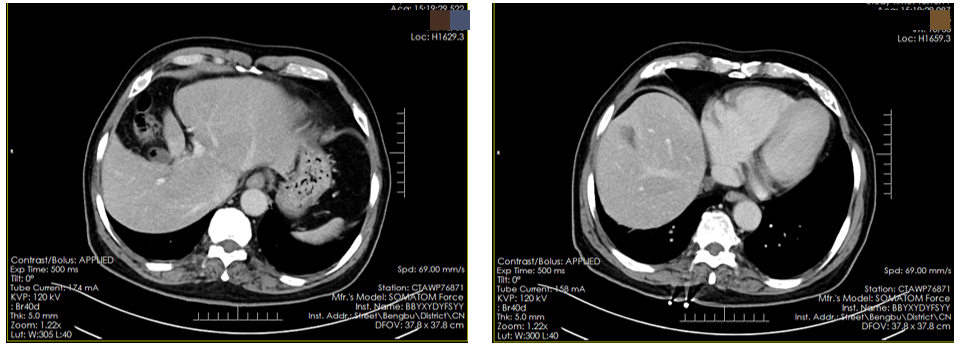

患者于2024年3月10日至2025年9月10日予以维迪西妥单抗(120mg,D1 Q3W)靶向化疗联合替雷利珠单抗(200mg,D1 Q3W)免疫治疗20周期。

期间定期复查CT,与治疗前(2024年3月)的基线CT相比,后续复查的CT(2024年8月及2025年8月)均显示肝脏转移病灶较前明显缩小(图4)。

疗效评价为部分缓解(PR)。

17.6.png图4. 腹部CT检查(左:2024年3月10日;右:2025年8月8日)